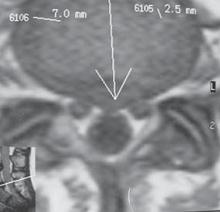

МРТ № 13

МРТ № 14

На МРТ № 13 наблюдается медиолатеральная грыжа межпозвонкового диска (заднебоковая)

На МРТ № 14 наблюдается фораминальная грыжа межпозвонкового диска с локализацией внутрь межпозвонкового отверстия